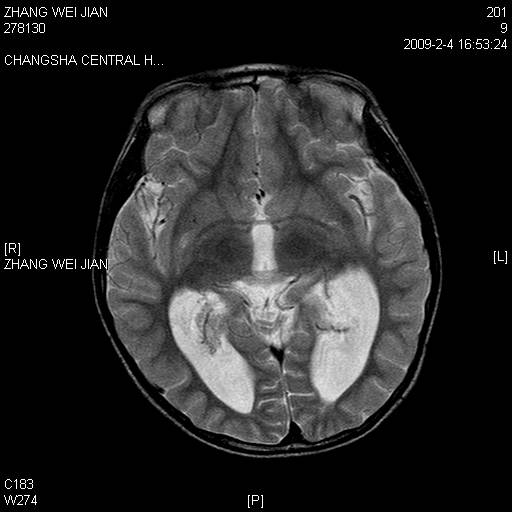

以下是引用guanaishengming在2009-2-6 22:51:00的发言:[br]脉络丛乳头状瘤

以下是引用随光逐影在2009-2-7 8:30:00的发言:[br]考虑双侧脑室脉络丛乳头状瘤并脑积水。

以下是引用同在2009-2-7 15:13:00的发言:[br]脉络丛乳头状瘤并脑积水。